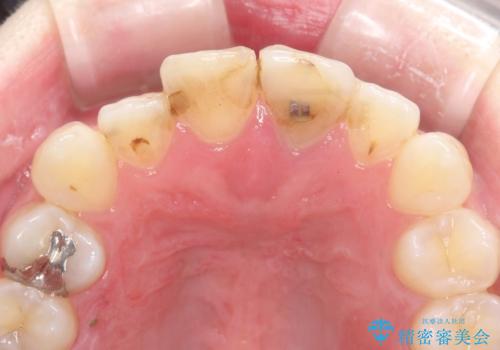

- 「前歯の色が気になる」を主訴に来院された患者様です。前歯が咬んでない開咬という状態のため、矯正治療を勧めましたが、患者様がご希望されなかったためオールセラミッククラウンで治療を行いました。右上1番は、神経の検査の結果、神経が死んでいたため根管療から行いました。左上1番は、金属の土台が入っていたのとラバーダムシートを使用せず根管治療が行われていたため、再度根管治療から行いました。その後ファイバーコアをたてオールセラミッククラウンで治療を行いました。

※右上1番の神経が死んでいた理由は定かではありませんが、保険治療で使用される材料では劣化により歯と材料の隙間が著しくなります。そこから細菌が侵入し神経が死んでしまう事があります。